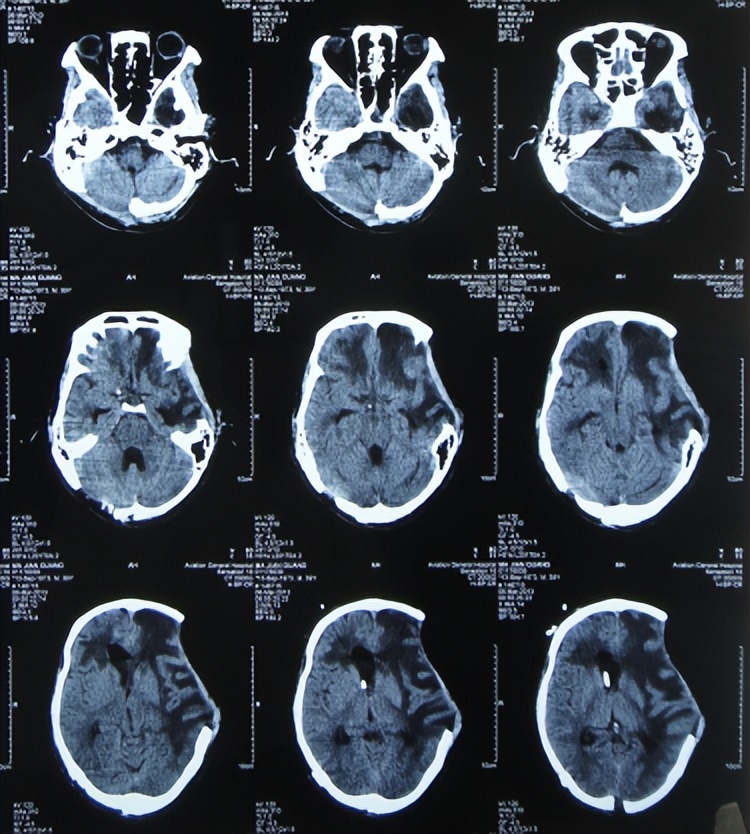

开颅术后11天,神志变醒,能简单言语;但开颅术后19天即2012年12月26日,发热最高体温38.5度,大小便*禁失**,查头颅CT是骨窗膨隆,脑室稍扩张( 图-5 );给予腰大池外引流术。

图-5: 2012年12月26日头颅CT

开颅术后28天即2013年1月4日(腰大池引流术后9天),认知能力好转,可自动进食,大小便可自控,但仍间断发热,查头颅CT示脑膨出变基本正常( 图-6 ),给予拔除腰大池引流管。

图-6: 2013年1月4日头颅CT

转院后继续行腰大池引流术,给予万古霉素、头孢哌酮钠及头孢曲松等抗炎治疗,开颅术后32天即2013年1月8日,查头颅CT认为脑室基本正常,但仍有水肿( 图-7 )。

图-7: 2013年1月8日头颅CT